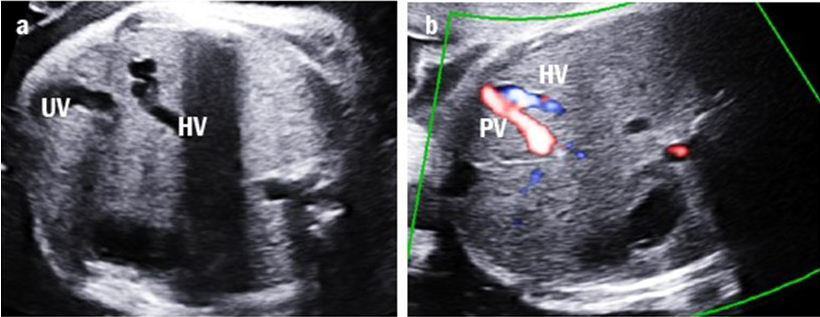

Four cases were classified as type IIIa UPSVS. They showed an abnormal connection between the PV and hepatic vein, which was observed as a tortuous and engorged vessel in the fetal liver (Fig. 4). However, the umbilical-portal-DV complex remained intact. Among these cases, three (75%) had birth weights below the 10th percentile and all had transient mild hyperammonemia. More importantly, none of them required shunt ligation surgery or liver transplantation.

Fig. 4.Intrahepatic portal-systemic shunt in case 11. (a) The tortuous and engorged hepatic vein (HV) is shown. (b) The intrahepatic portal vein (PV) is connected to the HV.